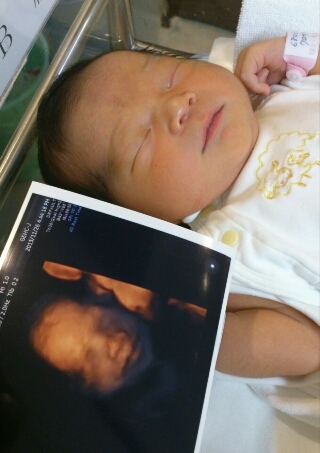

画像ありエコー写真と実際の顔を徹底比較!!4Dエコー撮影 お鼻の形は似てますがエコー写真ほど大きくはありません! 38週3日の4Dエコー 赤ちゃん大きくなっているのであまりよく見えなくなってきています。 補足 初めて13週に4dエコーを撮ったとき. 4Dエコーと実際の顔 こんばんは。 琉偉さんが妊娠中に4Dエコーというものを体験しました。 だそうです。 お腹の中でだんだん成長していく様子を残すことが出来ます。 こんな写真も。 ちなみに横浜市立市民病院には4Dエコーの設備がありません. 赤ちゃんの3d 4dエコー写真 実際の顔と比較してみたら似てた 旅 千葉県の北森ペット病院は現代社会に寄り添った動物のライフスタイルに重きを置いて、様々な疾患の研究を進めています。胎児の3D、胎生期の器官形成、胎児の心臓等、興味がつきません ;.

パパパッとパパ 4Dエコーと実際の顔を生後7日間の徹底比較! 画像で検証 息子が生まれる前、検診に行って4Dエコーの画像を見ては「パパとママどっちに似てるんかな」とか「イケメンかな」とかいろいろと妄想を膨らませていました。 ちなみにその. 出産前は、4dエコー(3dエコー)の写真を見つめながら、まだ見ぬわが子に思いを馳せたものです。 実際、エコー写真と産まれた後の顔は似ているのか? 4dエコー(24週・27週)/3dエコー(36週)と生後3日の写真を比較してみました。 スポンサーリンク. 画像ありエコー写真と実際の顔を徹底比較!!4dエコー撮影 でも4dエコーしてもらった時は 鼻がでかすぎて 、えっ?ってビックリしちゃいました。笑 エコー写真がどれくらい正確なのか産まれた息子と比較してみたいと思います!.

画像ありエコー写真と実際の顔を徹底比較!!4dエコー撮影 目はあまり似ていませんが鼻から口にかけては似ているような気がします。 31週3日の4dエコー 見た瞬間、鼻でかーーー!!って驚きま. 4Dエコーで初めて見たわが子の顔! 先生が撮った最高の1枚 産後に発症! むくみの裏に潜んでいた「妊娠高血圧症候群」 「常位胎盤早期剥離」で、母子ともに命の危機に! 退院後は帯状疱疹&産後うつまで 4歳の男の子と1歳の女の子を子育て中の 4dエコーとは、従来の2dや3d 実際に. エコー検査におけるダウン症児の顔の特徴について エコー検査では様々なことが調べられるのですが、 エコーの画像において顔の特徴が解るのかと言うと、1つだけ大きな特徴があります。 ダウン症児には典型的なものなのですが、.

今妊娠されている方、エコーって一体どれくらいの精度で実際の胎児の姿を映してるんだろうって思いませんか? 私は凄く気になりました。 なので、少し比較写真を乗せたいと思います。 とはいえ、我が子はエコーで全くお顔を見せてくれませんでした。. 4Dエコーと実際の顔を生後7日間の徹底比較!画像で検証 4Dエコー(超音波検査)とは?3Dエコーとの違いや料金などまとめ 妊娠32週目(32w0d~6d)のエコー写真とエピソード|妊娠9ヶ月 画像ありエコー写真と実際の顔を徹底比較!!4Dエコー撮影.

4dエコーと実際の顔を生後7日間の徹底比較 画像で検証 パパパッとパパ